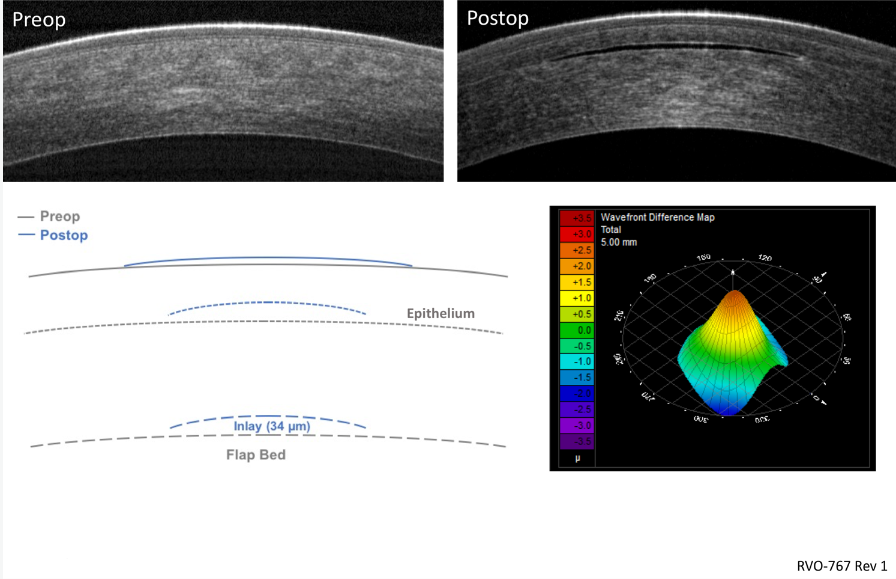

2. 角膜曲率重塑(图2)

植入物通过物理挤压改变角膜前表面曲率,形成多焦点光学区。如采用透明的、可渗透的、正弯月形的水凝胶植入物具有与角膜大致相同的折射率,植入物本身没有屈光力,但它通过增加覆盖植入物的角膜中心曲率半径来改变眼睛的屈光力。由于植入物边缘处比中心薄,前部角膜高度的增加从嵌入体直径前方区域过渡到中间区域,并返回未改变的角膜。

因此,它创建了一个超长椭圆状的角膜形状,从而形成多焦点角膜。用于植入物的水凝胶材料具有高渗透性,允许氧气和营养物质自由通过,因此确保了稳定的角膜条件。

(图2)